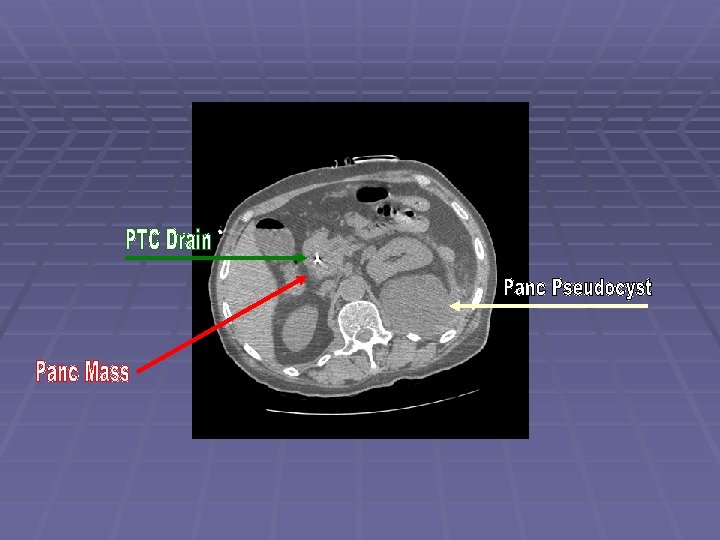

Patient DD 62 y. o. man with history of alcoholism and recurrent pancreatitis since the 1970’s, admitted to an outside hospital with jaundice MRI showed a large pancreatic head mass ERCP for biliary drainage – failed Complicated PTC by pancreatic tail pseudocyst formation with internalization - successful Patient left AMA and came to JMC EUS/FNA performed to obtain diagnosis

Endosonographic Evaluation EUS Large ~30 mm hypoechoic pancreatic head mass surrounding the intrapancreatic CBD with PTC drain seen within CBD Dilated PD to 5 mm with evidence of chronic pancreatitis FNA performed